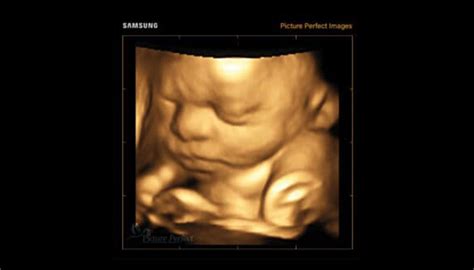

Ecografia ginecologică, în special cea 3D și 4D, reprezintă o metodă avansată de diagnosticare prin imagistică. Aceasta folosește unde sonore de înaltă frecvență pentru a crea imagini tridimensionale ale structurilor interne ale aparatului reproducător feminin, dar și ale fătului în timpul sarcinii.

Ecografia de trimestrul al II-lea, realizată între 18-23 de săptămâni de sarcină, permite evaluarea detaliată a morfologiei fetale. La această vârstă, copilul are dimensiunea potrivită pentru o examinare optimă a tuturor părților corpului. Adesea, este un moment de bucurie pentru viitoarele mame și familiile lor, când pot vedea imagini clare ale feței copilului, inclusiv în reconstrucție tridimensională 3D/4D.

Ecografia ginecologică 3D oferă o perspectivă detaliată asupra organelor reproductive, ajutând la diagnosticarea precisă a diverselor afecțiuni.

Unele clinici dispun de aparatură medicală modernă, precum ecograful ultra-performant Voluson E8, care permite obținerea de imagini 3D și 4D de înaltă calitate ale fătului.